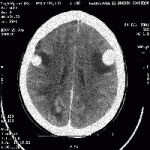

En dépit de plusieurs cycles de chimiothérapie réalisés à la fin de l’année 200, de nombreuses métastases furent trouvées dans le cerveau. Ces métastases avait continué à croître en dépit de plusieurs cycles de chimiothérapie qui s’étaient ensuivis. De plus, il y avait des métastases dans les glandes surrénales et dans l’aire colique. La patiente commença un cycle de traitements avec du bicarbonate de sodium intraveineux en mars 2001 qui fut capable d’arrêter la progression des localisations métastatiques. Il fut de ce fait décidé de commencer un cycle de traitement plus agressif, par administration de bicarbonate de sodium directement dans les masses par artériographie sélective des artères cérébrales, grâce à laquelle il fut possible de poser des cathéters dans les artères qui nourrissaient les formations tumorales. Les métastases apparurent avoir visiblement régressé après un cycle de 6 sessions réalisé à la mi-mai 2001.

Scans tomodensitométriques complets du

• 24 février 2001 (en haut)

• 30 mai 2001 (en bas)